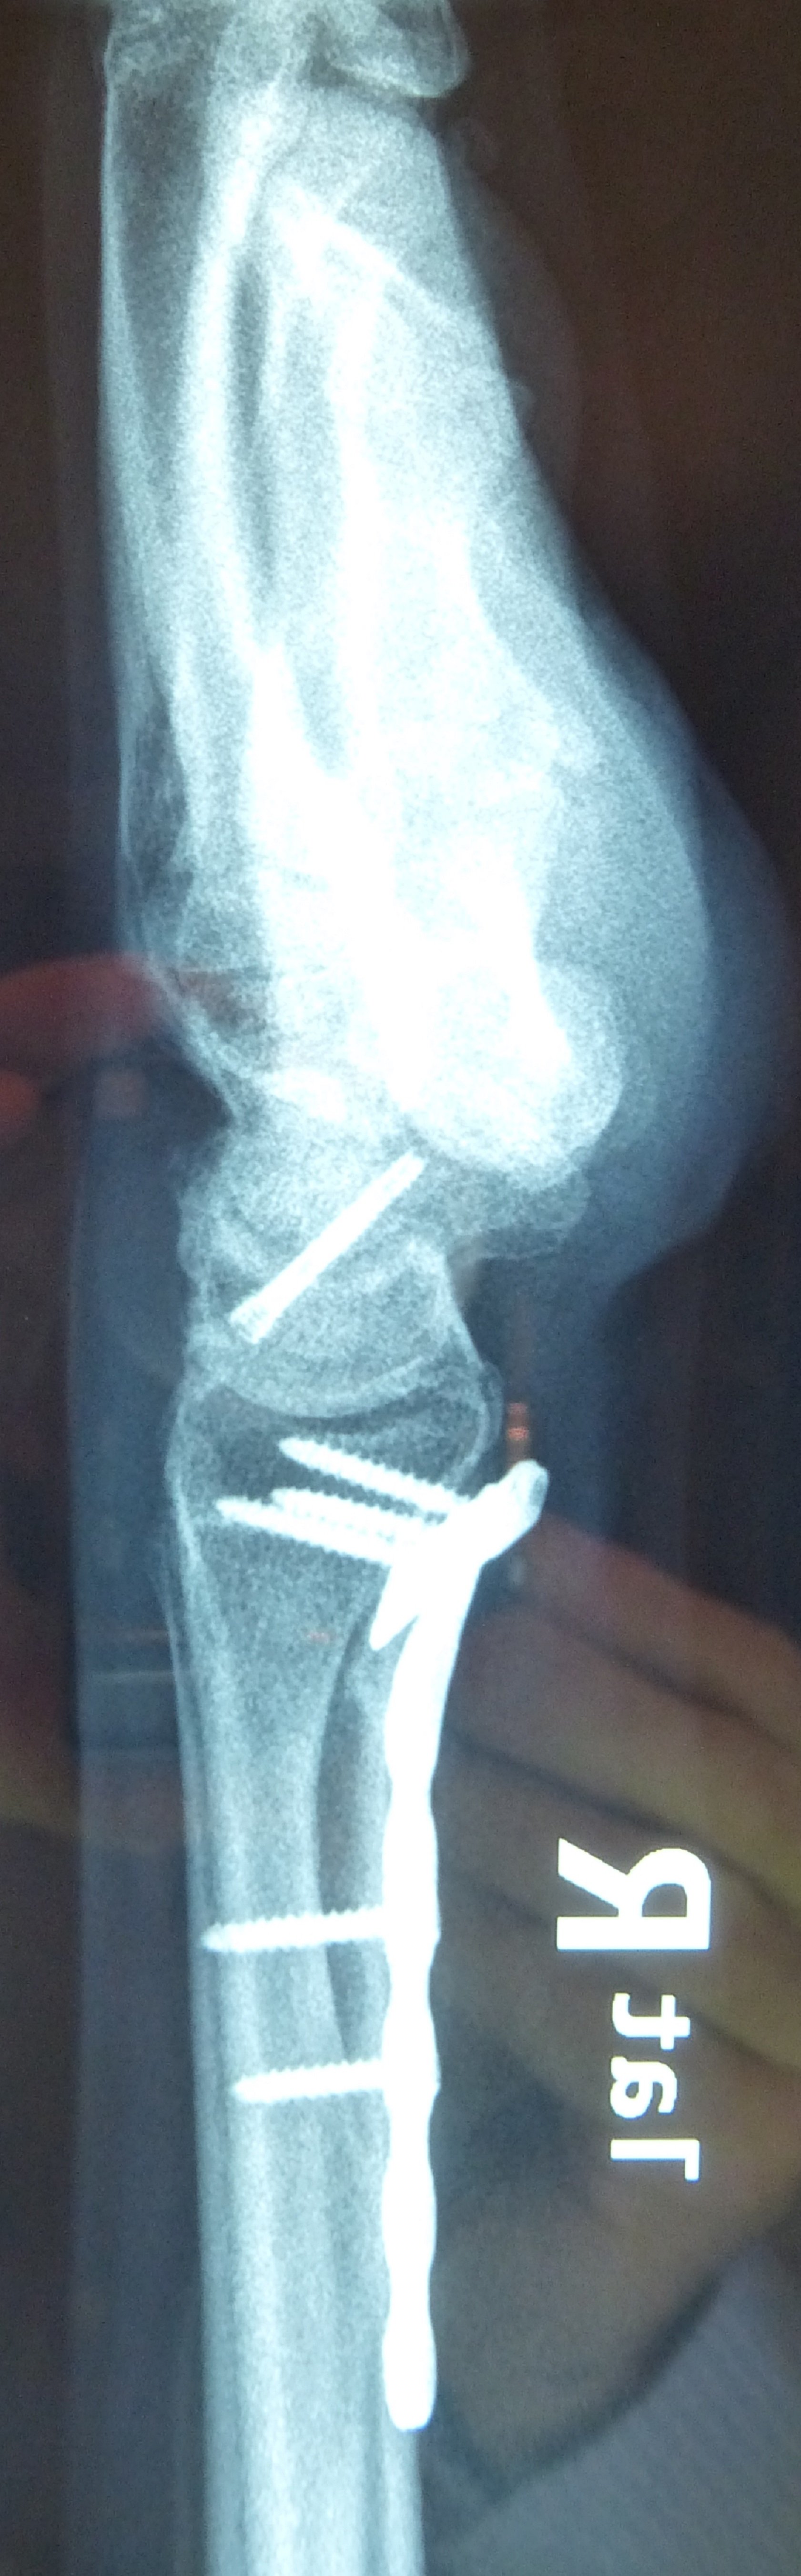

Η αντιμετώπιση της ψευδάρθρωσης του σκαφοειδούς είναι πάντοτε χειρουργική. Με ραχιαία ή παλαμιαία προσπέλαση αποκαθίσταται ο άξονας του σκαφοειδούς και σταθεροποιείται το σκαφοειδές με ειδική βίδα ή βελόνες, με παράλληλη τοποθέτηση οστικών μοσχευμάτων. Μπορεί επιπλέον να γίνει και οστεοτομία κλειστής σφήνας του περιφερικού άκρου της κερκίδος. Στις περιπτώσεις άσηπτης νέκρωσης το μόσχευμα πρέπει να είναι αγγειούμενο – για να προσδώσει αιμάτωση στο νεκρωμένο κεντρικό τμήμα – και λαμβάνεται με μικροχειρουργικές τεχνικές από το περιφερικό τμήμα της κερκίδος ή από άλλα τμήματα του σώματος

Διεγχειρητικά

Μετεγχειρητικά 1

Μετεγχειρητικά 2

Περίπτωση 2: Μετεγχειρητικά 1

Περίπτωση 2: Μετεγχειρητικά 2